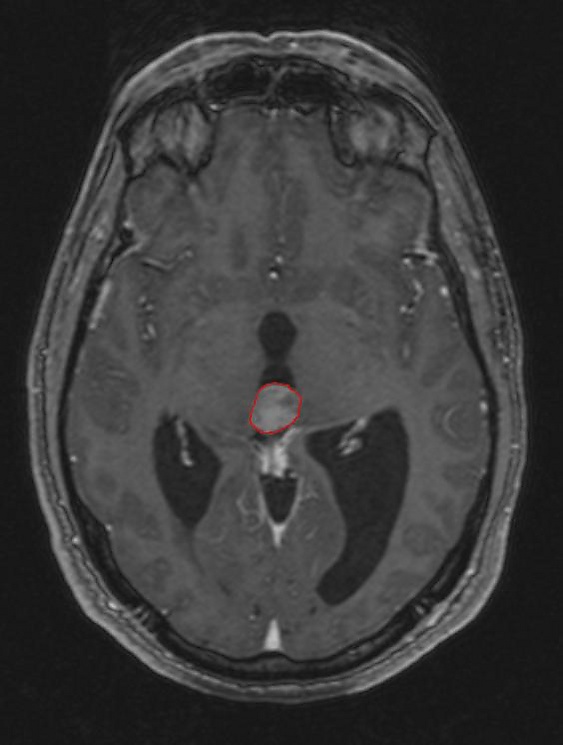

Пинеалома — опухоль головного мозга, исходящая из шишковидного тела. Это гетерогенная группа новообразований, локализующихся в пинеальной области (задние отделы III желудочка, область цистерны четверохолмия) и имеющих различное происхождение. Развитие пинеаломы может быть связано с опухолевой трансформацией пинеалоцитов, астроцитов или гоноцитов[2][3]. Опухоль, развившаяся из пинеалоцитов, в зависимости от степени дифференцировки носит название пинеоцитома, пинеальная паренхиматозная опухоль промежуточной дифференцировки, пинеобластома. Опухоли астроцитарного происхождения имеют типичное строение. Наиболее характерным для астроцитомы является медленный, инфильтративный рост.

Симптомы опухоли обусловлены её расположением. Наиболее частыми симптомами являются головные боли, тошнота и рвота. Они обусловлены повышением внутричерепного давления вызванного обструктивной гидроцефалией, которая возникает при сдавлении опухолевой массой водопровода мозга и нарушением циркуляции спинномозговой жидкости.

Компрессия верхнего двухолмия опухолью приводит к синдрому Парино — невозможности вертикальных движений глаз, небольшой дилатации зрачка. Возможно развитие отёка соска зрительного нерва